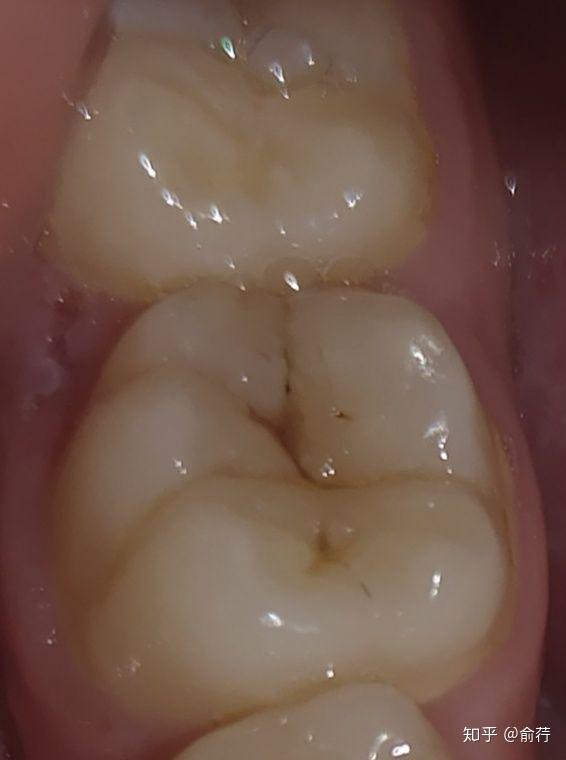

大牙上有浅色的黑线是怎么回事?是蛀牙吗?

牙上黑色的东西一定是蛀牙嘛(大牙上有黑黑的东西)(1)